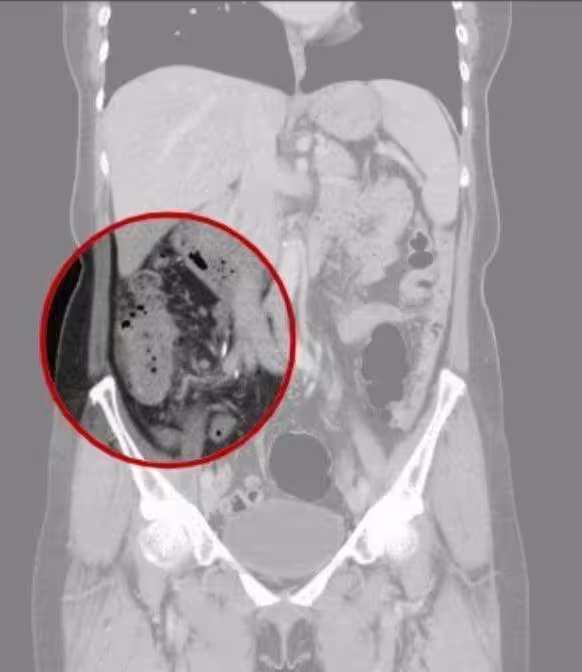

無大腸癌相關病史 台中女確診已癌末據了解,已婚的吳女無大腸癌相關家族史與病史,但4月時她突然受到腹痛、血便及噁心困擾,就醫檢查時驚見自己升結腸有8*5公分腫瘤,同時胃部也有5*3公分的高惡性風險胃腸道基質瘤,